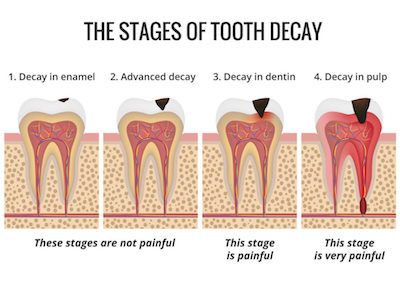

Beberapa hal dapat merusak gigi kita dengan lebih cepat seperti gigi retak gigi berlubang. Ada beberapa cara yang bisa dilakukan untuk mengatasi sakit gigi berlubang antara lain. Untungnya ada cara mengatasi sakit gigi berlubang tanpa obat.

Jika Anda sedang sakit gigi penting untuk mencari tahu apa yang menjadi akar masalahnya. Gigi baru mulai berlubang. Obat-obat alami penghilang sakit gigi ini ada di sekitar dapur sehingga Anda tak perlu repot pergi ke apotik.